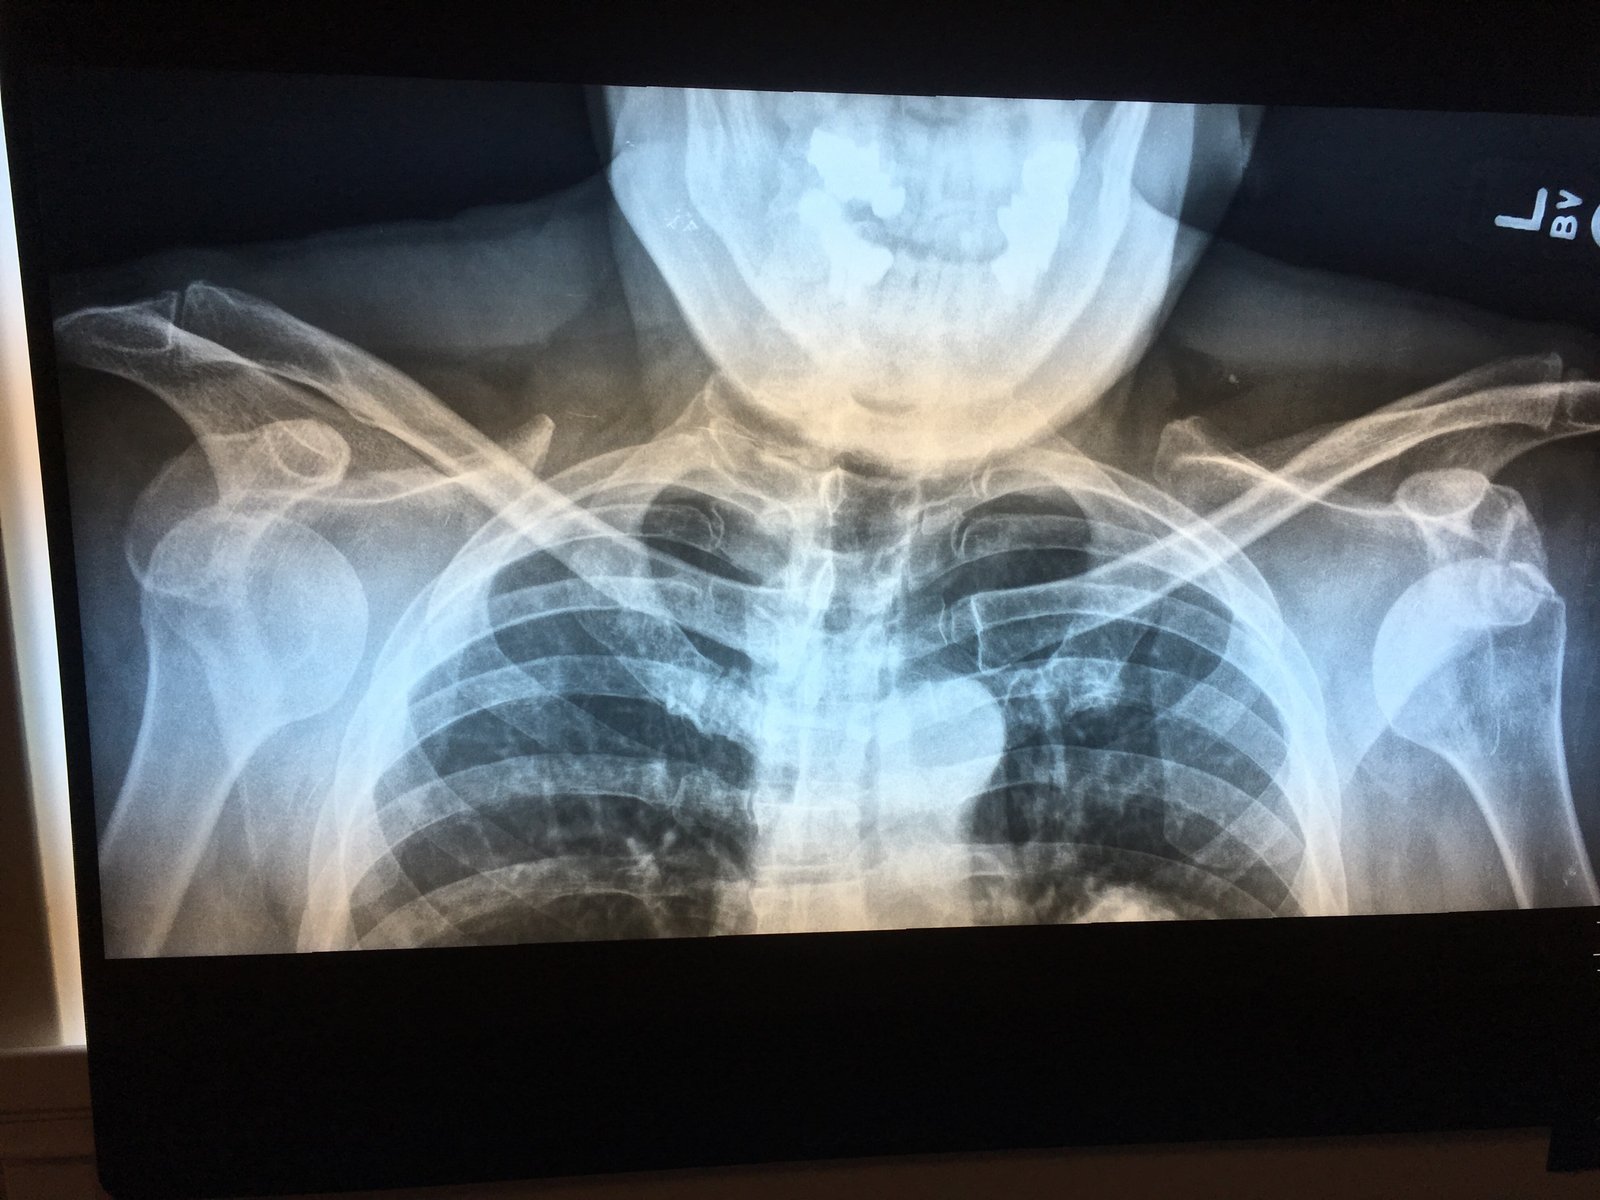

The patient was a 60-year-old male who had been skiing when he abruptly fell with arms overhead (superman position). The patient immediately experienced bilateral shoulder pain and was rushed to the clinic associated with the ski resort. On physical exam, he had bilateral step-off deformities and both shoulders were abducted approximately 15 degrees with elbows flexed at 90 degrees. He promptly received X-rays which demonstrated bilateral anterior shoulder dislocation and left humeral head fracture.

An anteroposterior chest X-ray demonstrates bilateral shoulder dislocations. Both the right and left humeral heads (blue lines) are displaced medially, anteriorly, and inferiorly from their normal positions in the glenoid fossae (red lines), thus signifying bilateral anterior dislocations. There is also a fracture of the left humeral head at the greater tubercle (green arrow).

In this case, the left-sided reduction was completed easily by forward flexion of the arm with acromion pressure and medial rotation of the scapula without analgesia. The right shoulder required administration of analgesia and two reduction attempts with successful reduction using external rotation and abduction. Repeat X-rays were obtained showing adequate reduction. The patient was neurovascularly intact before and after reduction. The patient was immobilized in slings and orthopedic follow up with physical therapy was prescribed.